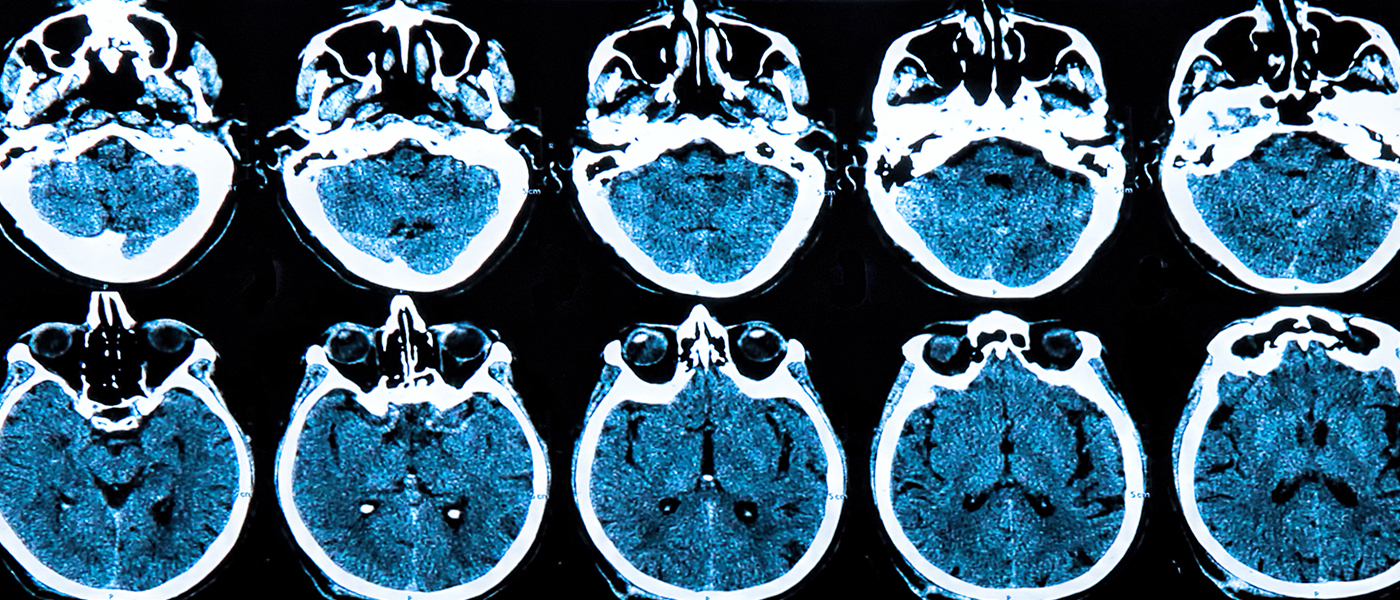

A drug that has already been approved to treat leukemia is now closer to being approved for use against the debilitating brain diseases, parkinson’s and alzheimer’s. There are more than 5 million people currently living with Alzheimer’s disease in the US and another million living with parkinson’s. This drug has the potential to change the lives of not just these millions of sufferers, but also their countless friends and family who suffer along with them.

Years of research studying these neurodegenerative diseases has allowed for new treatments like this to be developed. A better understanding of how these diseases work and how they impact the brains of sufferers is leading to better potential treatments.